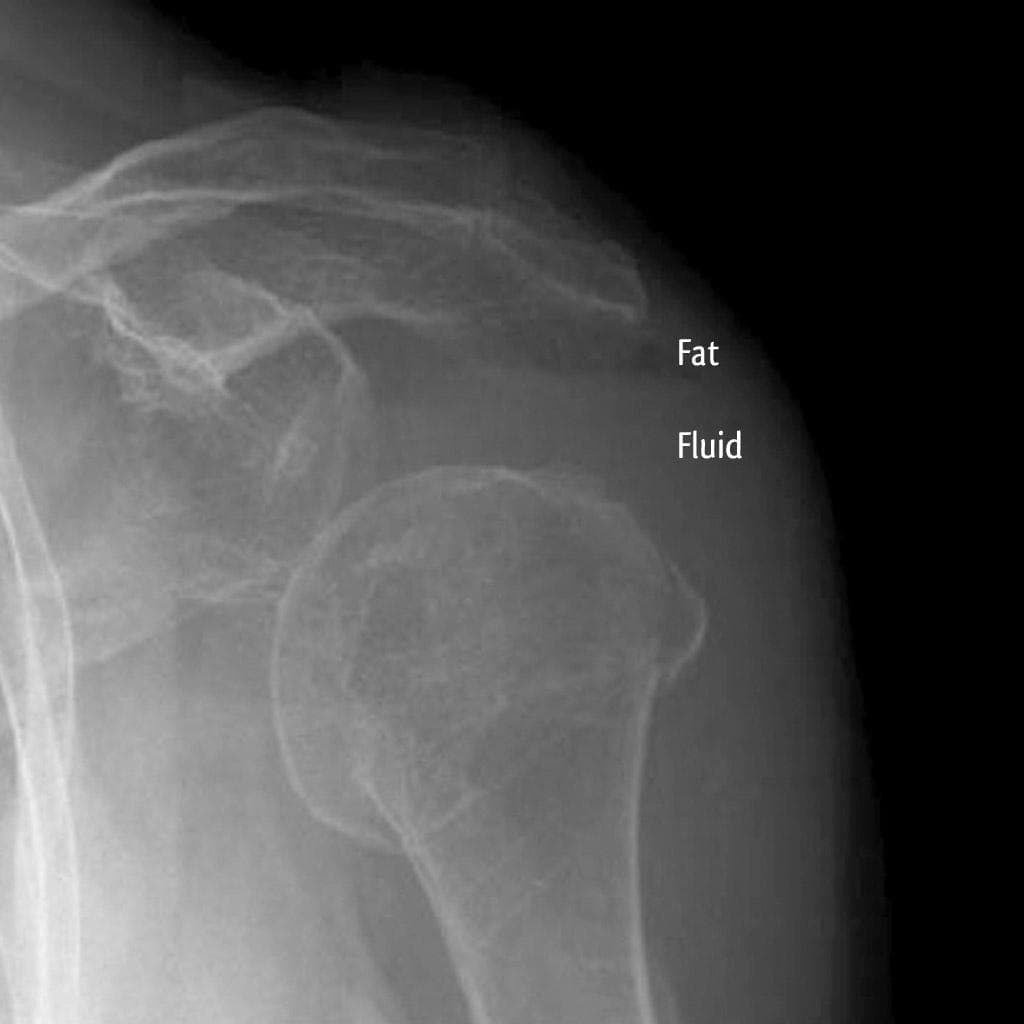

Chỏm xương cánh tay bị trật xuống dưới kèm gãy vụn đầu trên xương cánh tay và di lệch mấu động lớn. Lưu ý tư thế dạng của xương cánh tay. Hình ảnh X-quang sau nắn chỉnh tình trạng trật khớp vai. Không phát hiện tổn thương Bankart xương. Gãy vụn đầu trên xương cánh tay. THẢO LUẬN: Trật khớp vai xuống dưới, còn được gọi là luxatio erecta, là loại trật khớp vai ít gặp nhất. Trong trật khớp vai xuống dưới, cánh tay được giữ ở tư thế dạng do chỏm xương cánh tay bị kẹt dưới bờ xương ổ chảo. Trật khớp xuống dưới có thể giống với trật khớp vai ra trước kiểu dưới ổ chảo, trong đó chỏm xương cánh tay nằm ngay dưới mỏm ổ chảo của xương bả vai trên các bình diện thẳng và nghiêng.